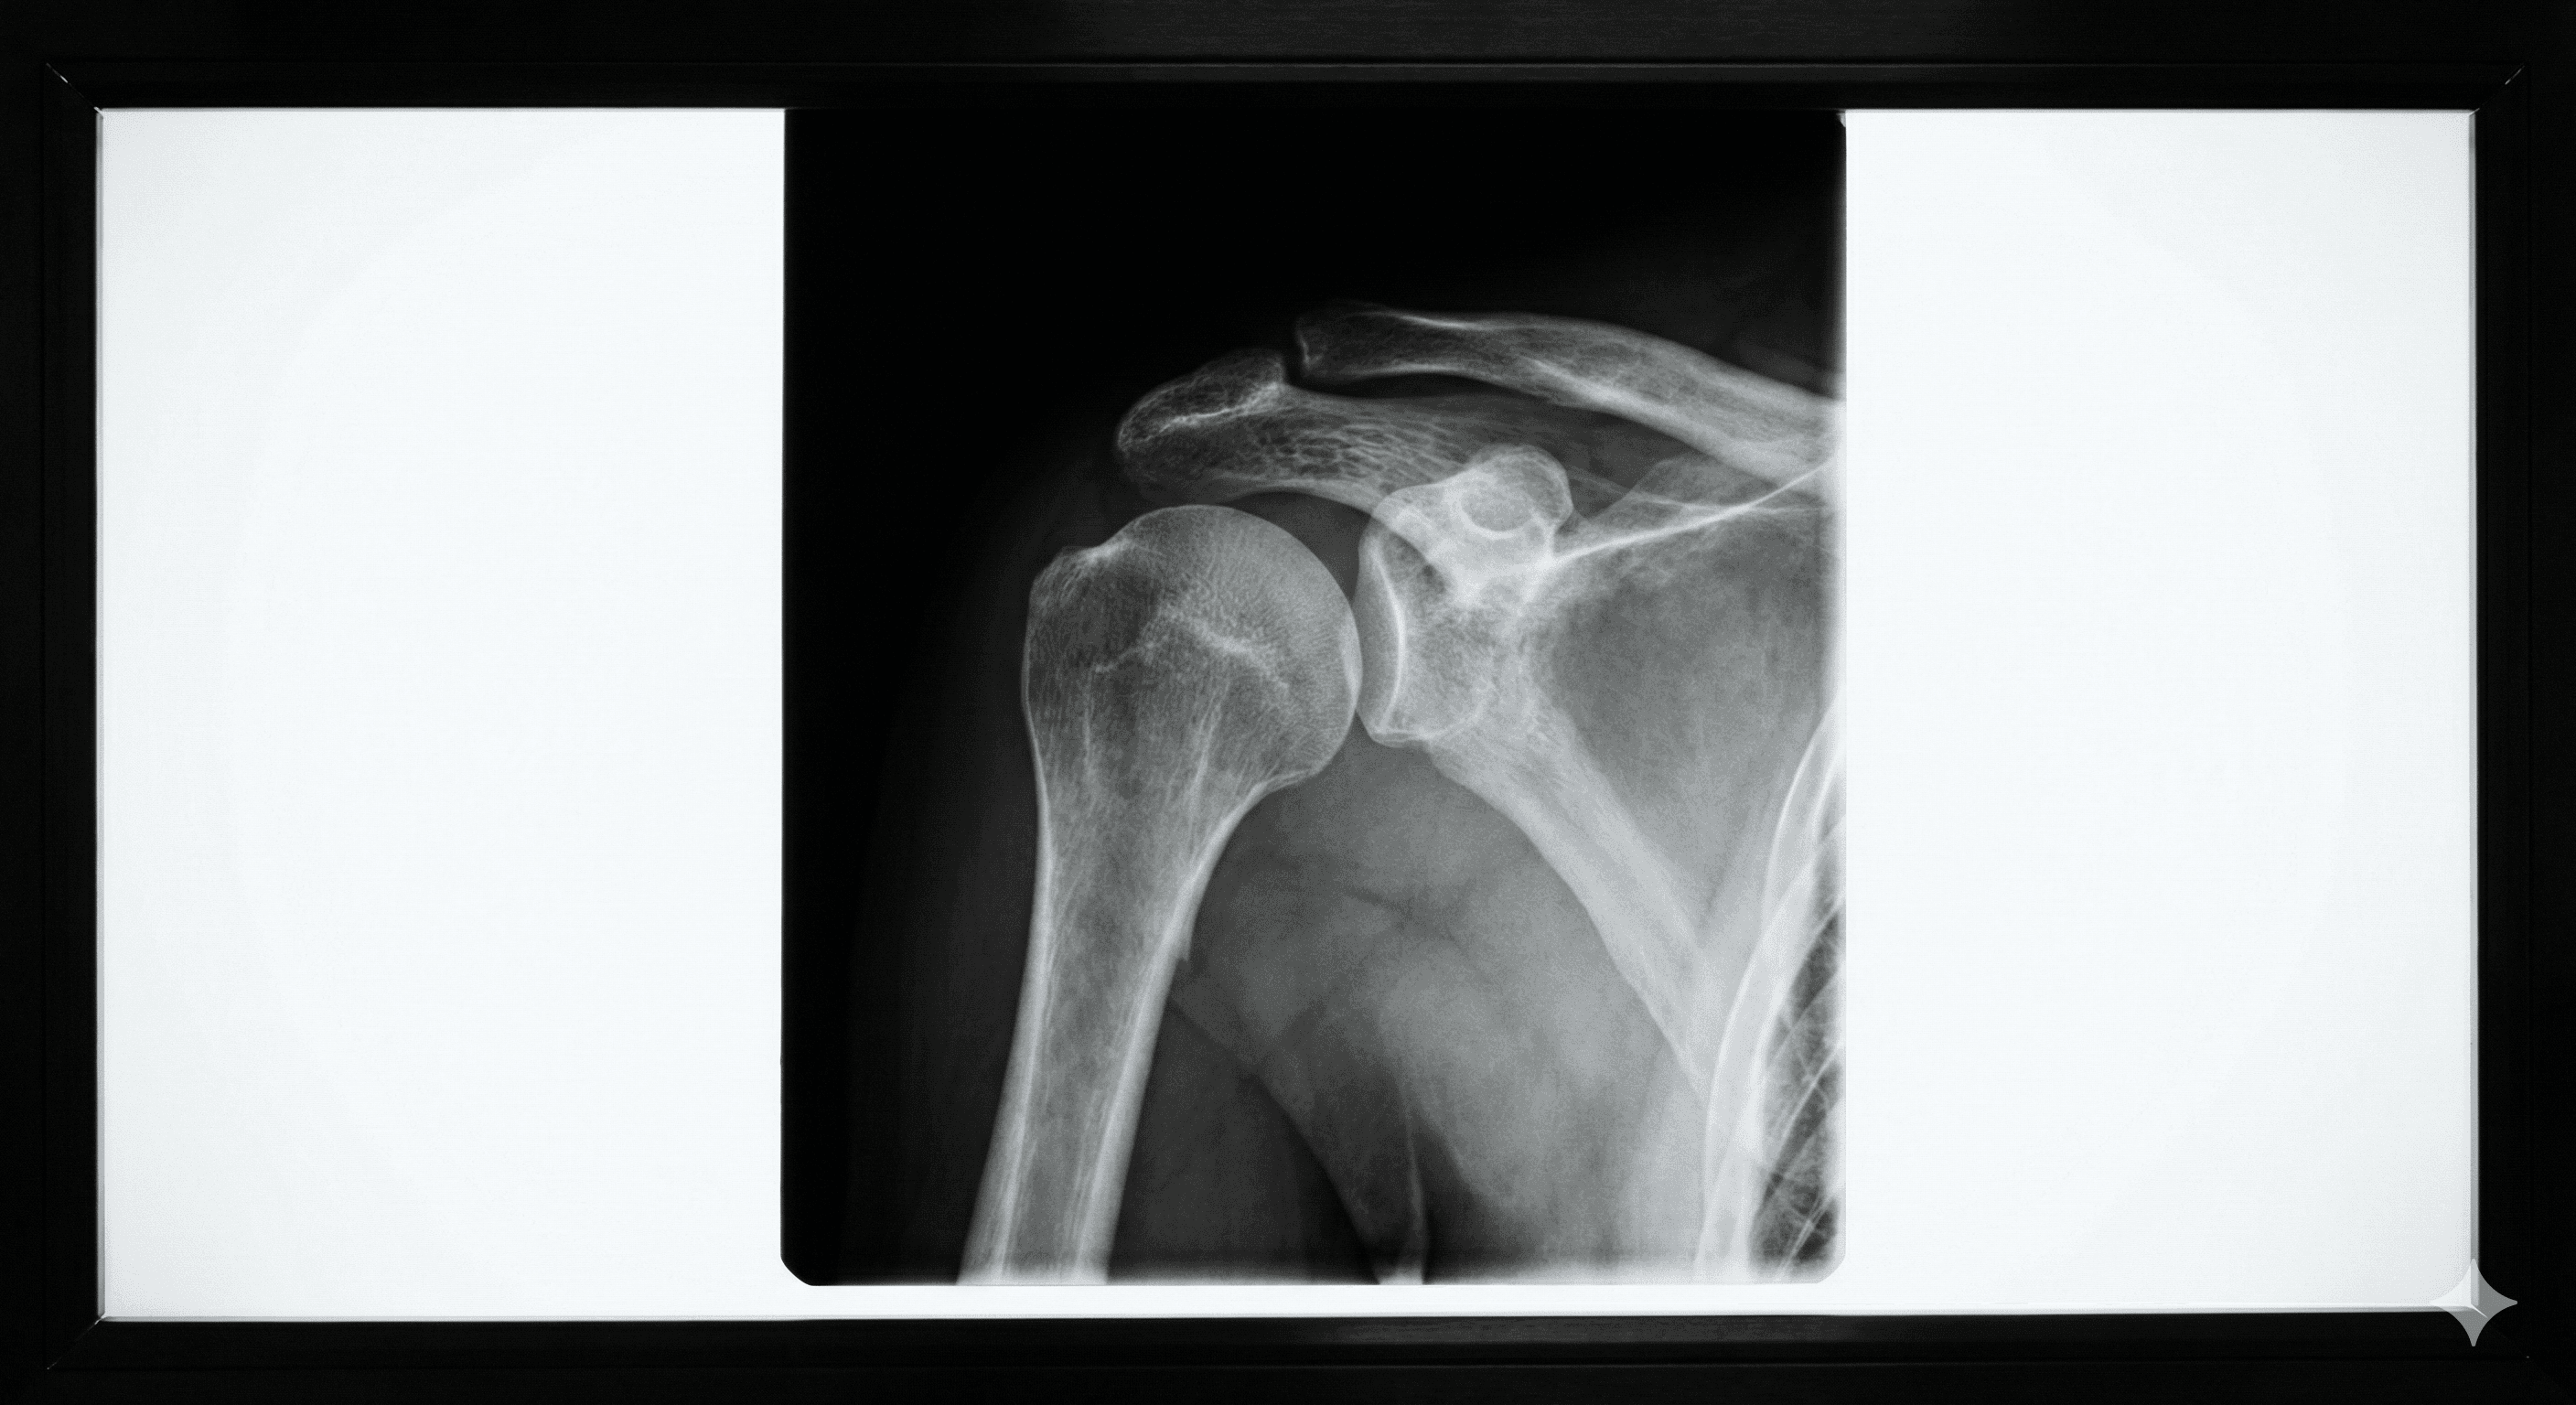

Lesión en la que los extremos de los huesos se salen de su posición normal en una articulación.

Leer más